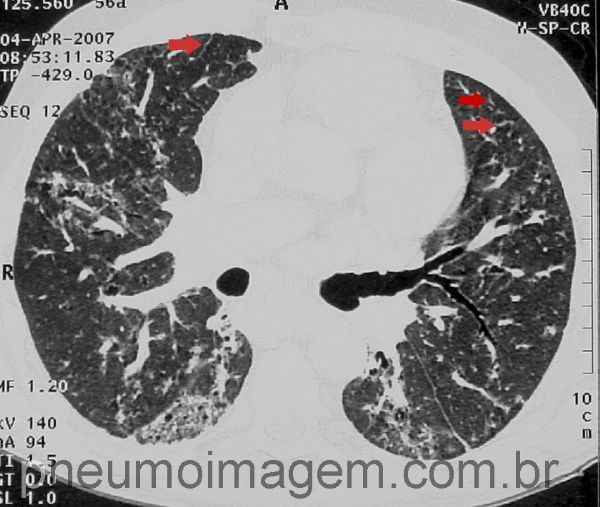

Esclerose sistêmica progressiva (esclerodermia). Redução do volume de ambos os pulmões devido às opacidades intersticiais com faveolamento pulmonar.

Padrão de Pneumonia Intersticial Não Específica (PINE).

Predomínio de opacidades em vidro fosco periféricas, áreas em favo de mel menos intensas que na UIP. Observa-se espessamento intralobular subpleural (seta vermelha).

Chaves: non specific interstitial pneumonia; NSIP; bronchiectasis.